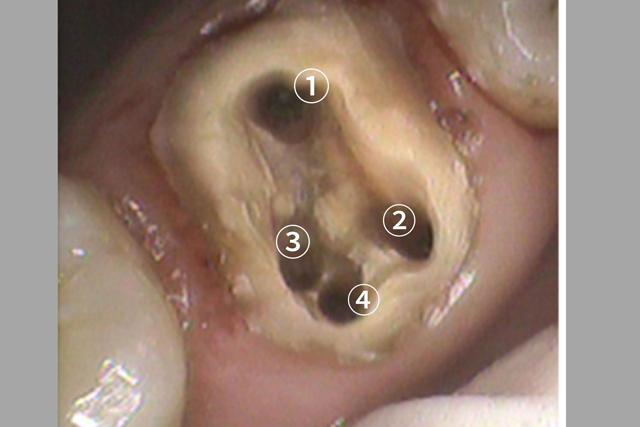

②銀歯を被せた歯がまた虫歯を再発する

銀歯と歯は歯科用の接着材でペタンとくっつけています。

しかし、正確にいうとぴったりとくっついているわけではありません。

封鎖性が非常に弱いため隙間があるのです。

銀歯を入れる際に歯との隙間を接着材で埋め、

くっつけているだけ、です。

隙間があるので隙間からは細菌は侵入し放題です。

お口の中には目に見えない何百億の細菌が存在します。

侵入し放題の虫歯菌により、せっかく治療した歯の中に虫歯が再発します。

銀歯のセメントも劣化してくるので、古い銀歯の中で、元々の歯が真っ黒になっていたといったこともよくあります。